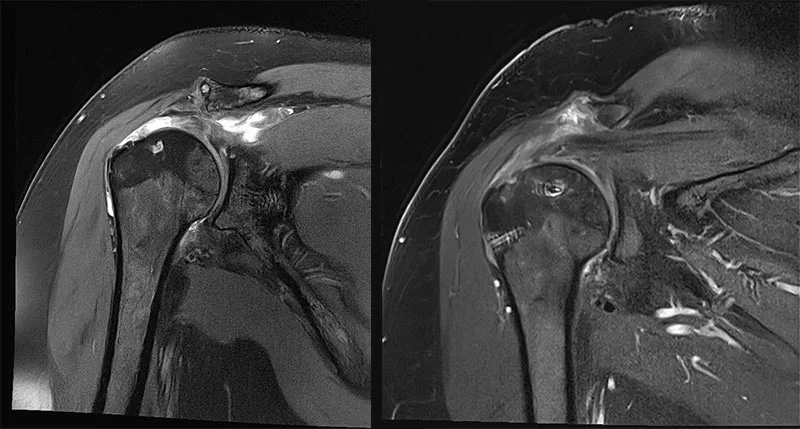

Sehnenriss Schulter

Die orthopädische Versorgung eines Sehnenrisses beinhaltet die Diagnose des Risses durch Bildgebung und klinische Untersuchungen, gefolgt von einer individuell angepassten Behandlung, die je nach Schweregrad des Risses konservative Methoden wie Physiotherapie, Ruhigstellung und Schmerzmanagement oder chirurgische Interventionen wie eine Sehnennaht oder eine Rekonstruktion umfassen kann.

Der Sehnenriss in der Schulter im Detail